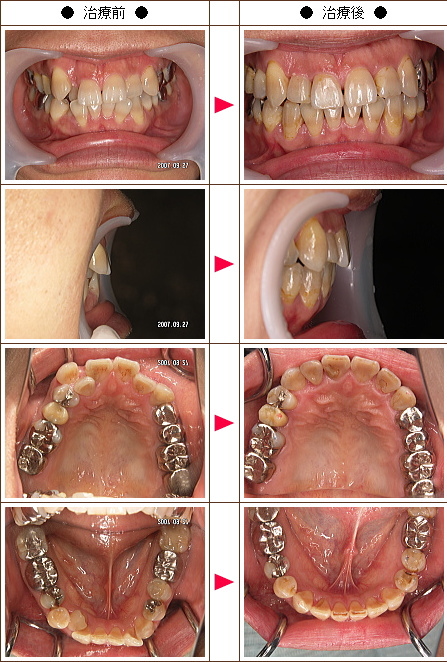

☆歯のデコボコ矯正症例[42歳 女性]